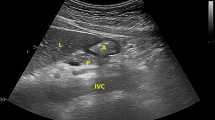

Nephrectomy and renal ischemia-reperfusion injury

Mice were anesthetized with 3% isoflurane in 2 L O2 and kept at 37 °C with an electrical heating pad. Following a 2-cm abdominal incision, the vascular pedicles of the right and left kidneys were identified under a microscope. First, the right renal artery, vein, and ureter were ligated and cauterized. Immediately after, the right kidney was dissected and flash-frozen in liquid nitrogen. Second, the left pedicle was clamped for either 23 minutes for young male and old male mice or 34 min for young female mice with S&T vascular micro-clamps (FST 18055-03, Fine Science Tools). Of note, the survival experiment was performed as a bilateral clamping of both pedicles for 35 minutes. A darkening of the kidney was observed to ensure that the pedicle had been successfully clamped.

Hepatic ischemia-reperfusion injury

Liver IRI was performed as described previously14. Briefly, mice were anesthetized with 3% isoflurane in 2 L O2 and kept at 37 °C with an electrical heating pad. Following a 2-cm abdominal incision, the vascular pedicles of the median lobe and left lateral lobe were identified under a microscope. An atraumatic S&T vascular micro-clamp (FST 18055-03, Fine Science Tools) was placed across the portal vein, hepatic artery, and bile duct just above the branching to the right lateral lobe for 35 minutes. Blanching of the lobes was observed to ensure that the artery had been successfully clamped. After 35 minutes of ischemia, the clamp was removed.